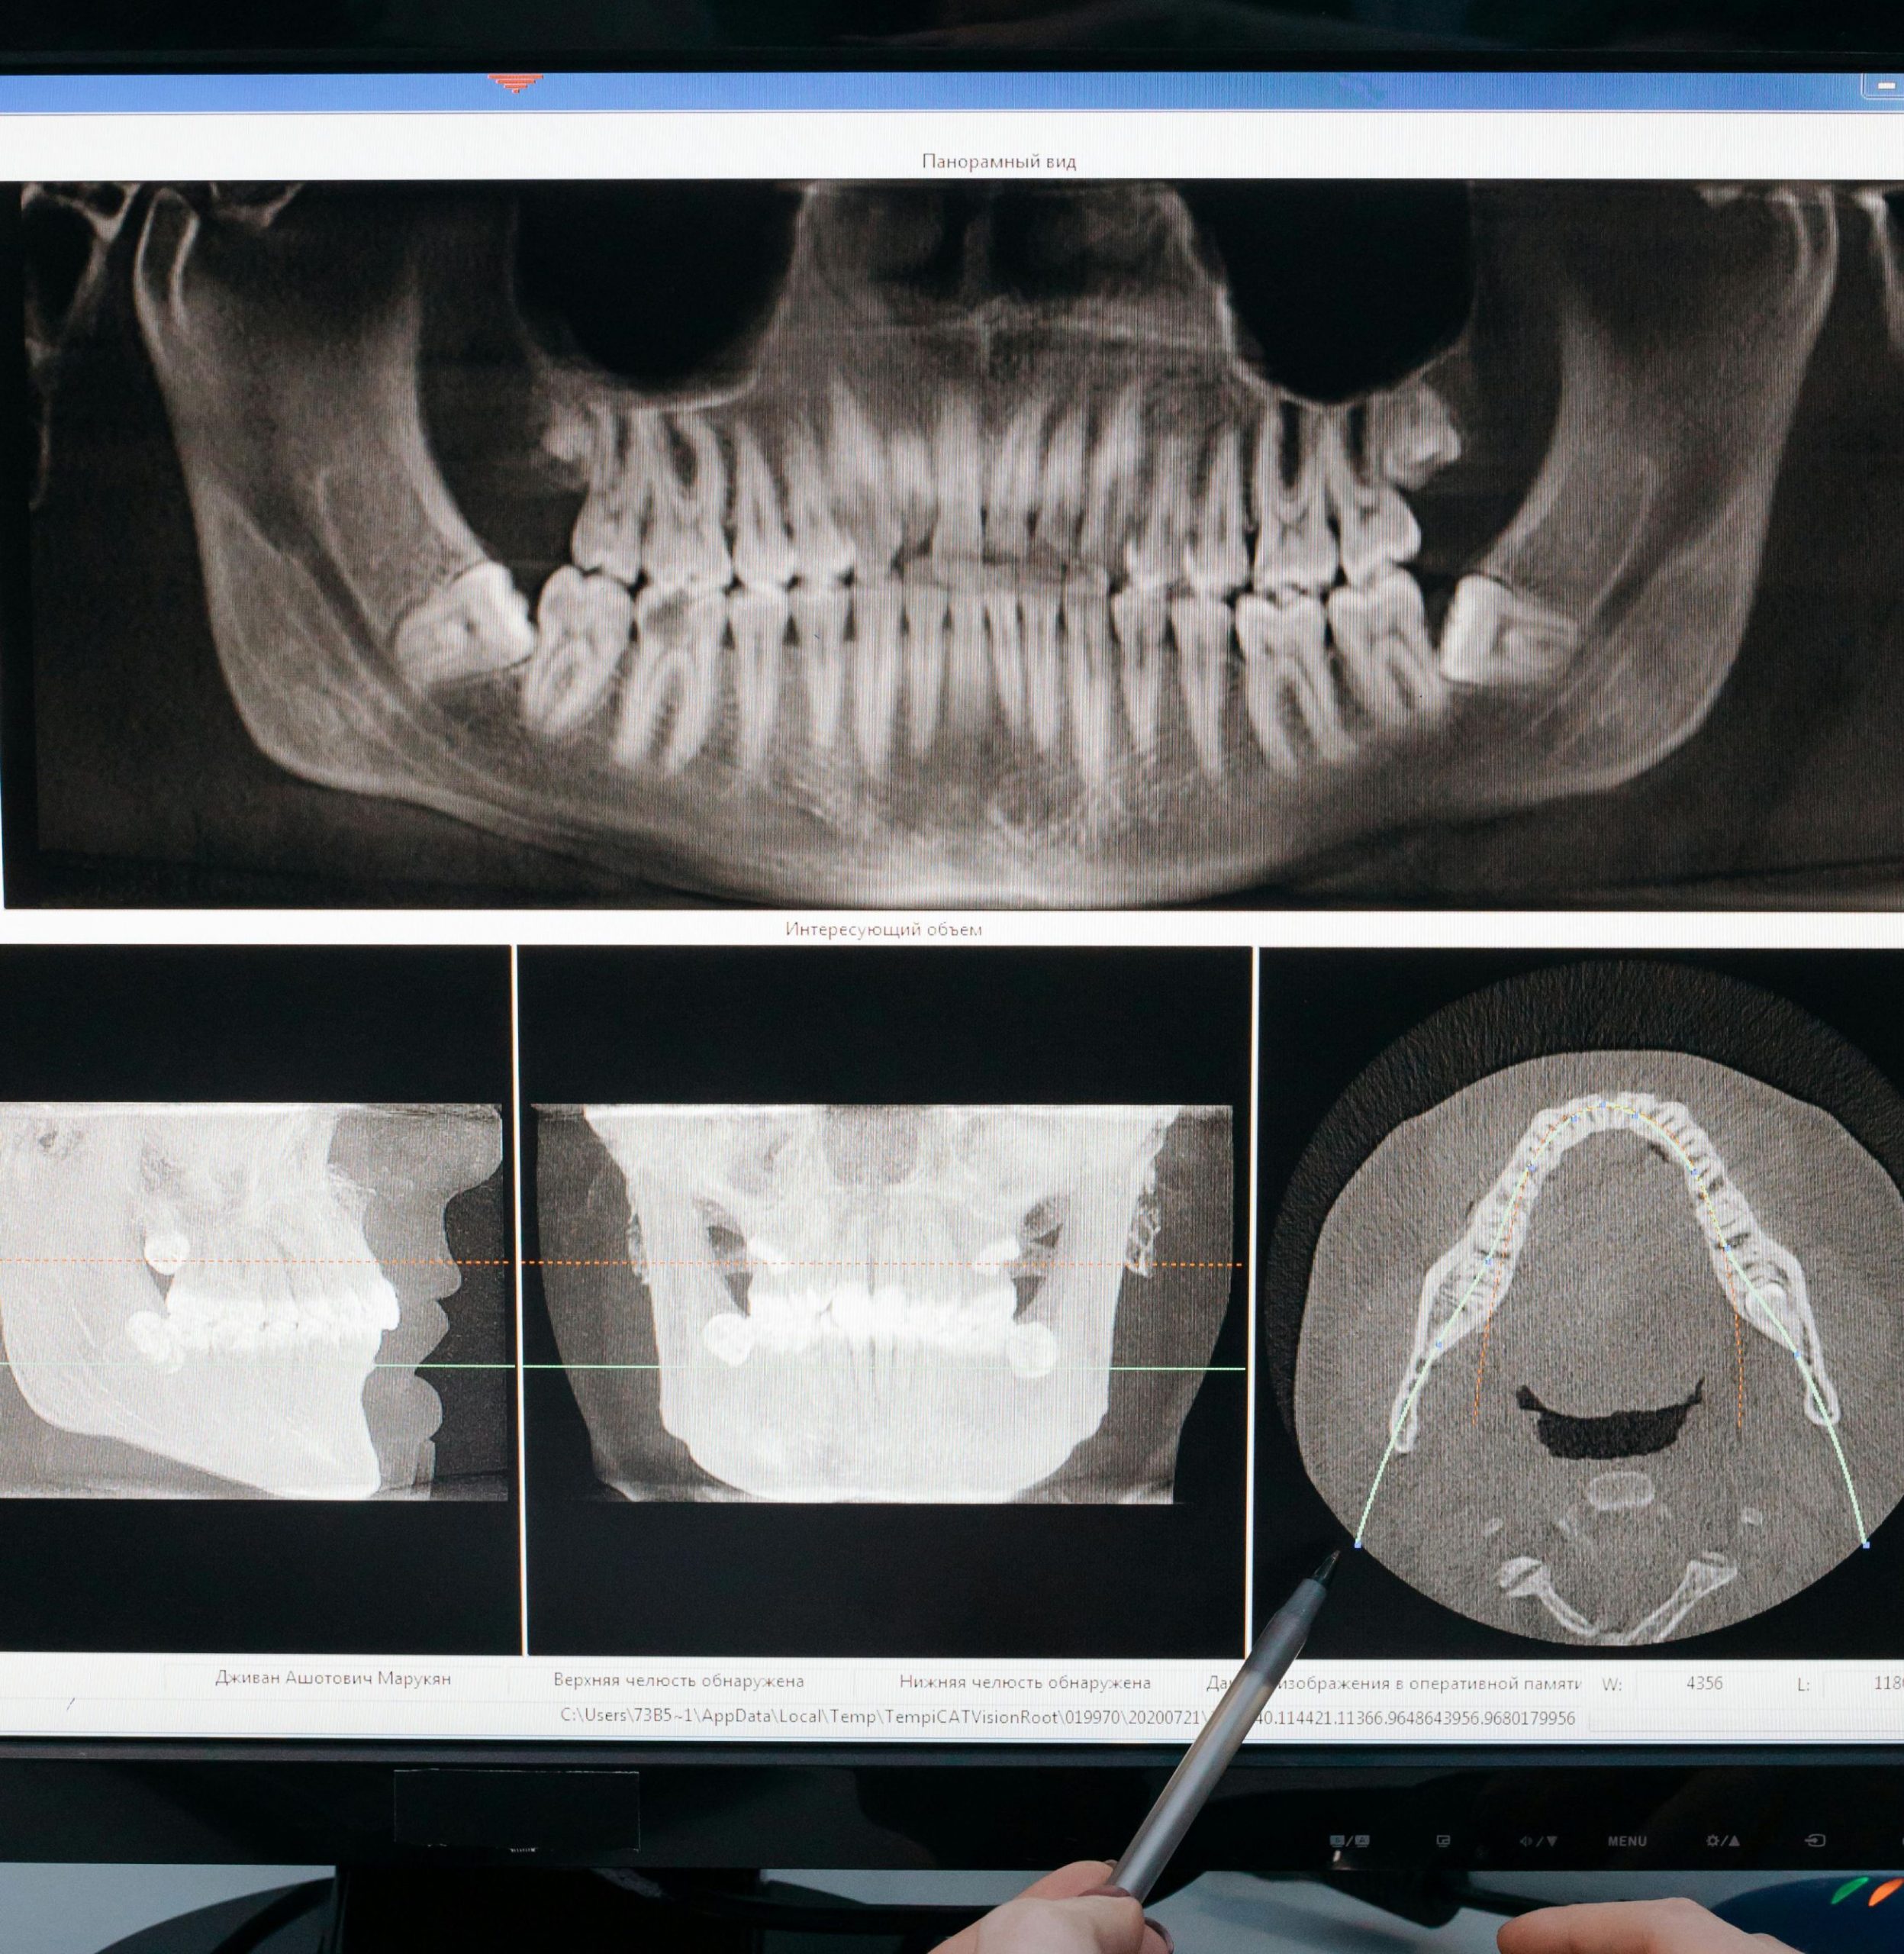

Кроме того, если зуб мудрости полностью не прорезался и частично скрыт в десне, это может стать причиной инфекций, которые трудно лечить. Такие ситуации требуют вмешательства стоматолога хирурга. Стоматология использует стоматологический рентген для оценки положения зуба и принятия решения о его удалении.